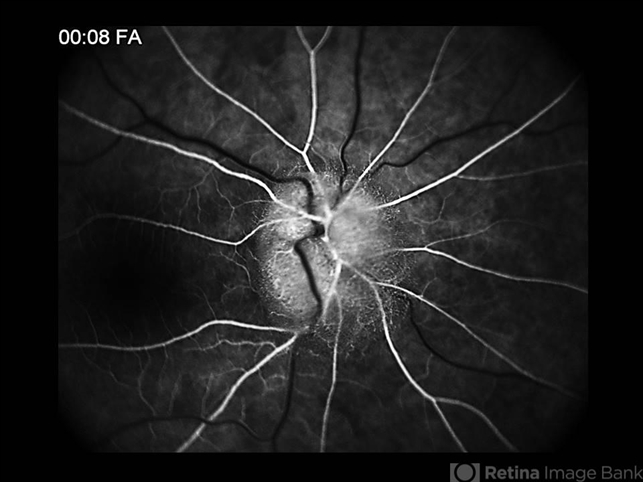

Topcon TRC-50 Ex - Angulation of field photo of 35 Degrees. Digital system OphthaVision - Description

- Patient female, 51-year-old, white. attended the clinic with the complaint of low vision, flash, right in the eye and headaches. In the examination of the fundus of the eye were observed important changes such as the Papilledema unilateral. Just confirmation more detailed examination angiographic.